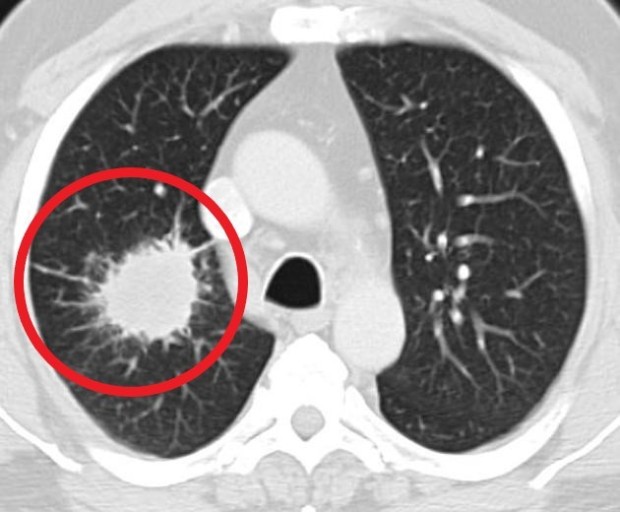

폐암 증상에는 기침, 체중 감소 흉통, 혈담 즉 피가 섞인 가래, 호흡곤란 등이 있지만, 위 증상은 다른 폐 질환에서도 나타날 수 있는 증상으로 구분하기가 어렵다. 그리고 폐암 초기에는 특별한 증상이 없는 경우가 대부분이라서 최근 흡연뿐 아니라 미세먼지 등 여러가지 요인으로 폐암이 발생하는 경우가 많아 정기검진으로 조기에 발견하는 것이 중요며 폐암 검진을 위해서는 특히나 저선량 흉부 CT를 촬영하는 것이 좋다라고 전문가들은 말하고 있습니다..